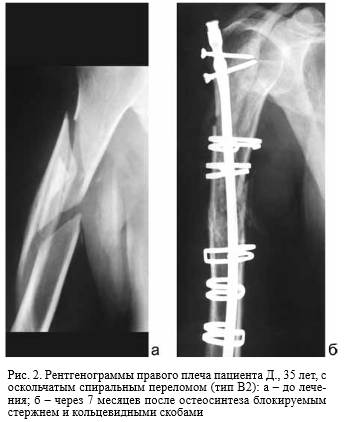

Боли после остеосинтеза

Боли после остеосинтеза 109 фото